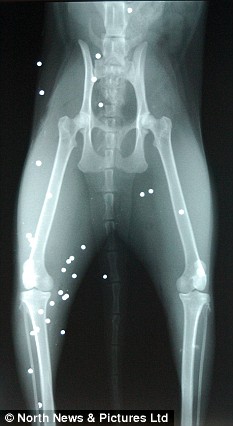

X光顯示羅西的身體里嵌入多達(dá)50枚子彈

兩歲的貓咪羅西11日遭到了一幫社會氓流的襲擊。等到主人特蕾西發(fā)現(xiàn)它的時候,這個可憐的小家伙正倒在血泊中,努力拖動被打瘸的后腿并痛苦地哀嚎著?!拔耶?dāng)時驚呆了,它渾身都是血,”特蕾西說。“羅西一共有大約50處傷口,獸醫(yī)取出了其中20枚子彈,剩下的30枚將永遠(yuǎn)嵌入它的身體。我太憤怒了,簡直不能相信有人竟然如此殘忍地對待小動物。”

獸醫(yī)特納表示:“這是我第一次救治一只被子彈擊中的貓。50枚子彈對于貓而言實(shí)在太多了,可它十分幸運(yùn)。”